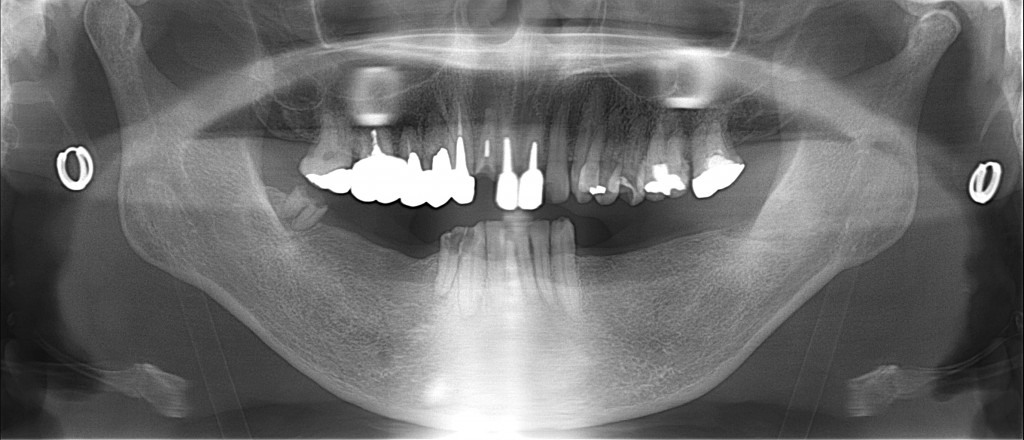

初診時レントゲン

↑のように下の奥歯がない状態の場合は

前歯でご飯を食べるので

上の前歯に強い突き上げる力が作用します。